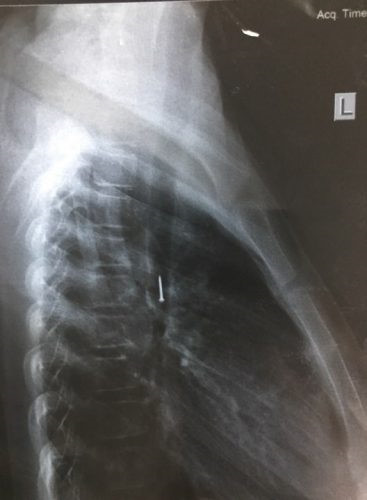

Các bác sĩ khoa Hô hấp – Bệnh viện Nhi Trung ương vừa phẫu thuật nội soi gắp thành công chiếc đinh ghim sắt đế nhựa trong phế quản bé gái Nguyễn Thị Thương (12 tuổi, trú tỉnh Sơn La).

Sau tai nạn, bé ho sặc sụa, khạc ra máu, nôn nhiều nên được người nhà đưa đến Bệnh viện Đa khoa Mộc Châu (Sơn La) khám. Tại đây, qua chụp X-quang các bác sĩ xác định lồng ngực cháu bé có dị vật hình đinh ghim. Bé Thương được chuyển tới Bệnh viện Nhi Trung ương để theo dõi và tiếp tục điều trị.

Tại Bệnh viện Nhi Trung ương, các bác sĩ tiến hành chụp X-quang cho thấy có dị vật là một chiếc đinh ghim dài khoảng 1,5 cm nằm ở vị trí thành ngực của bé gái. Các bác sĩ đã hội chẩn và quyết định phẫu thuật nội soi lấy dị vật ra khỏi lồng ngực của bé.

Ca phẫu thuật nội soi gắp dị vật được tiến hành ngay trong buổi chiều 18/5. Sau hơn 10 phút làm thủ thuật, các bác sĩ đã lấy ra được một chiếc đinh ghim bằng sắt dài 1,5 cm, loại đế nhựa để ghim giấy nằm trong phế quản của bé Thương. Chiếc đinh ghim được lấy ra kịp thời nên đã không nguy hại đến tính mạng của bé. Hiện sức khỏe bé đã ổn định và đã được ra viện.